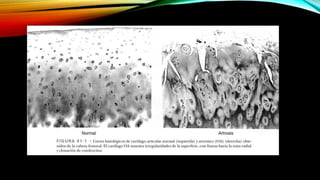

CAMBIOS MORFOLÓGICOS

• En la OA precoz, la superficie del cartílago articular se vuelve irregular y se

evidencian fisuras superficiales en el tejido; se altera la distribución de

proteoglucano.

• A medida que el trastorno empeora, las fisuras son más profundas, las

irregularidades de la superficie aumentan y el cartílago articular acaba

ulcerándose, exponiendo el hueso subyacente.